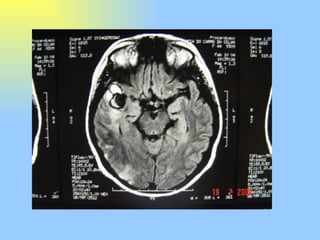

Este documento descreve o caso de uma paciente de 43 anos que apresentava fortes dores de cabeça do lado direito, náuseas, vômitos e sensibilidade à luz e ao som, diagnosticadas como enxaqueca em salvas. Exames de imagem revelaram um aneurisma gigante na artéria cerebral média direita, e depois a paciente desenvolveu fraqueza parcial do lado esquerdo do corpo devido a um coágulo sanguíneo.